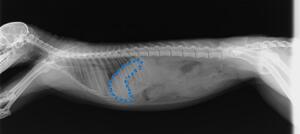

↓2026年のレントゲン写真。

リリーは元気も食欲もあったのですが、このまま腫瘤が大きくなってしまうと胃や腸を圧迫して食欲がなくなってしまったり、突然腫瘤が破裂してしまったりする可能性もあったため、予後を考えると切除できるのであれば切除したいと考えていました。

しかし、巨大な腫瘤。手術もとても難しいものになりますし、そもそも当園にある検査機器では腫瘤全体の形状を把握できないため、手術適応なのかどうか判断することすら難しい状況でした。CT検査であれば、腫瘤がどうなっているのかわかるのではないか…